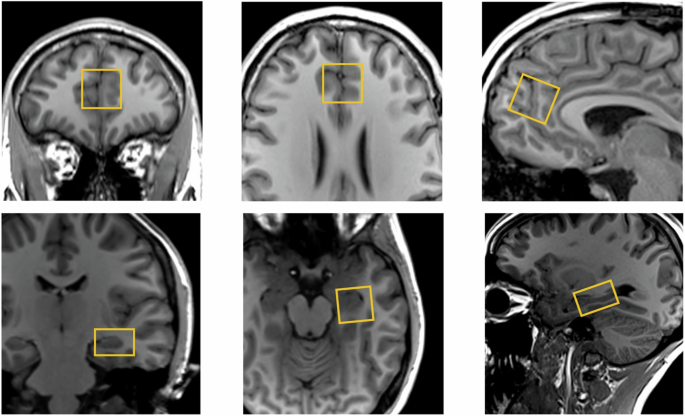

We conducted single voxel 1H-MRS as reported previously [10]. We used the Point RESolved technique (echo time = 30 ms, repetition time = 3000 ms, 96 averages, Vector size = 2048, Bandwidth = 2500 Hz). Before MRS acquisition, the B0 homogeneity across the voxel was automatically optimised then manually fine-tuned with the first-order shim gradients to achieve a water linewidth \(\le\) 18 Hz. A 20 × 20 × 20 mm voxel was placed in the ACC, immediately anterior to the genu of the corpus callosum in the midline (Fig. 1). A 20 × 20 × 15 mm voxel was placed in the left hippocampus, angled parallel to the anterior horn of the temporal lobe, placed just posterior to the amygdala, avoiding the petrous bones (Fig. 1).